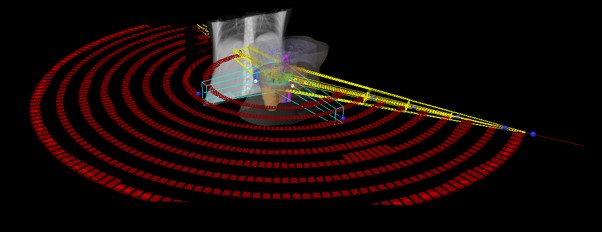

SABR meta hepatis et pelvis (21.11.2017.)

Rezultat – 47 mjeseci nakon RK

potpuni nestanak tretiranih lezija